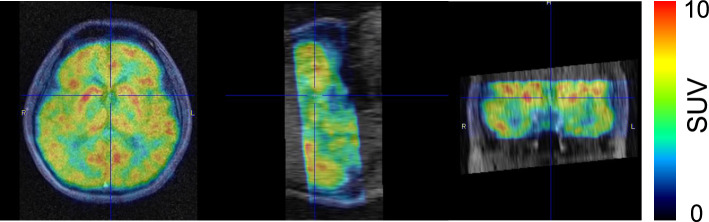

Background: Combined PET and MRI scanners allow for simultaneous image acquisition, simplifying the interpretation of both PET and MRI images. We prototyped an insert-type PET that can convert a standalone MRI to a PET-MRI system, named Add-on PET. In Add-on PET, we fully integrated the PET modules into a head radiofrequency (RF) coil so that PET detectors can be close to the brain and avoid placing the RF coil in the field of view of PET. This study aimed at confirming the feasibility of human brain simultaneous PET and MRI imaging using a prototype of add-on PET.

Results: The PET images obtained with and without simultaneous MRI sequences were identical (Pearson's correlation coefficient, r = 0.953). Background noise was observed in the MRI images acquired during the PET scan; however, the noise decreased when the count rates of PET declined. The MRI obtained simultaneously was used for attenuation correction, providing well-correlated voxel values with those using the CT-based attenuation correction method (r = 0.989).

Conclusions: The simultaneous PET and MRI images were performed without noticeable artifacts. There was no significant interference in PET images caused by the simultaneous MRI sequence; however, some background noise was observed in the MRI, likely due to the electric current from PET modules used for counting a clinically used radioactivity concentration.